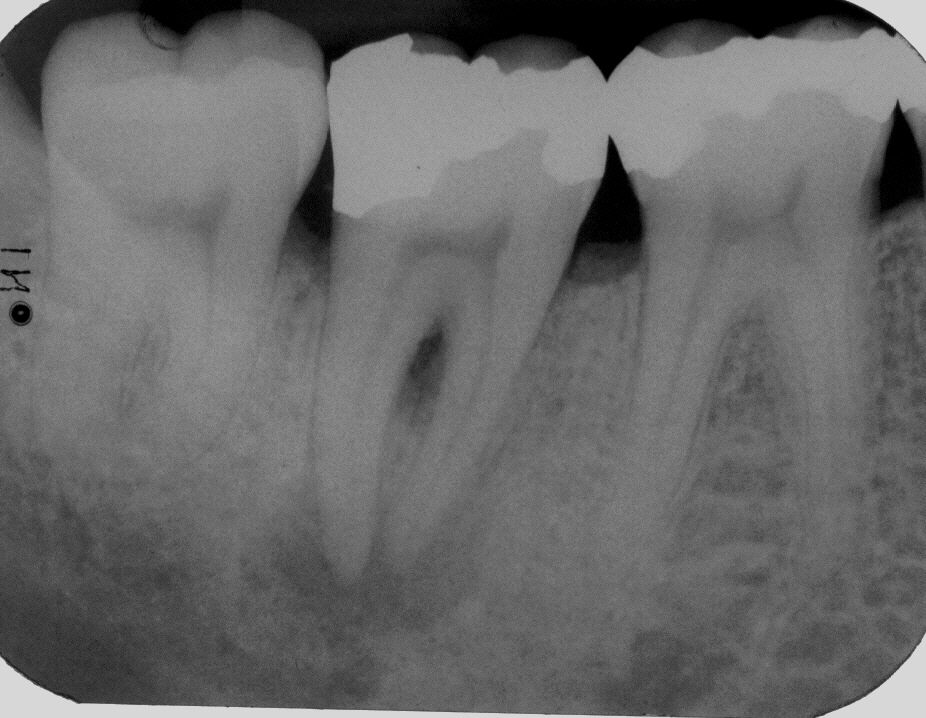

Röntgenologischer Ausgangsbefund

Röntgenologischer Ausgangsbefund im August 1996 bei Zahn 44 mit chronisch apikaler Parodontitis; Zustand vor umfangreicher ZE-Neuversorgung. Erste Therapie der Wahl ist in diesem Fall immer die konventionelle Wurzelkanalbehandlung ohne primär chirurgische Intervention